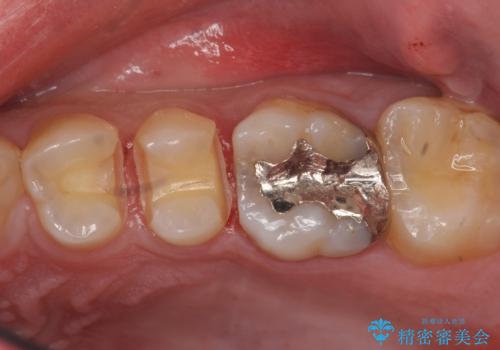

コンタクトカリエスの治療

- 虫歯の検査のために来院された患者さまです。

レントゲンで診査したら、歯と歯の間に虫歯(コンタクトカリエス)が見られたので

e-maxインレーで治療を行いました。